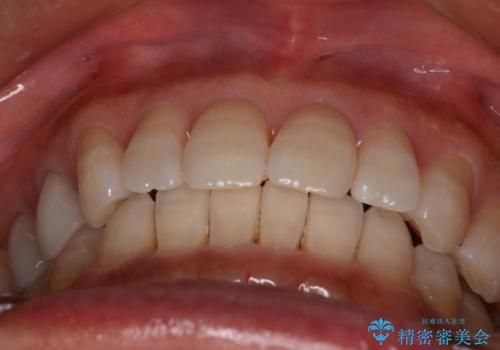

【インビザライン】下前歯だけを治したい

- 下前歯のがたつきにより唇を巻き込んでかんでしまい痛いため矯正をしたいという主訴で来院されました。今回は下顎前歯のみという強い希望があり、下顎のみのインビザライン矯正をしました。

叢生を改善するためのスペースはIPRと拡大を行いました。治療後は唇を巻き込んでしまう主訴が改善し、ご満足していただけました。